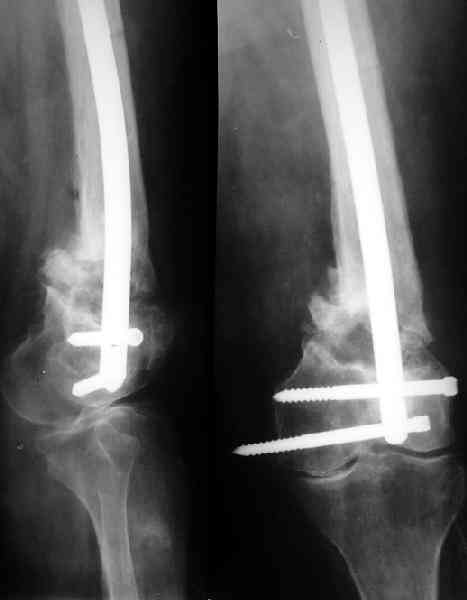

По всей вероятности, после перелома бедренной кости, случившегося 15 лет назад, у больной сформировался псевдоартроз в дистальной эпиметафизарной зоне. Травма этого года привела, с моей точки зрения, к частичному разрушению псевдоартроза, а не к повторному перелому. Учитывая амнестические данные о больной, я бы не спешил с оперативным вмешательством, а предложил бы больной съёмный ортез и нагрузку на ногу в течение двух-трёх месяцев. Такой промежуток времени при данной патологии не ухудшит условия для оперативного вмешательства, если оно потребуется, но позволит более определённо установить необходимость такового, если конечность не станет опорной или больная сама станет настаивать на оперативном вмешательстве.

Что касается самого оперативного лечения, то оно представляет значительные трудности и положительный исход его не столь очевиден. С моей точки зрения, адекватная фиксация любой металлоконструкции в дистальном отломке бедренной кости невозможна. Поэтому вариантов вмешательства два: либо ВКДО с фиксацией голени (что, учитывая конституцию больной и сопутствующую патологию, менее приемлемо), либо антеградный БИОС с прохождением стержня через коленный сустав и дистальным блокированием в проксимальном эпиметафизе большеберцовой кости. И в том и другом случае потребуется открытая репозиция и костная пластика (возможно в несколько этапов). Вопросы восстановления длины конечности и функции коленного сустава на данном этапе лечения не главные. Цель оперативного лечения – восстановление опорной функции конечности и сращение перелома.

Пример подобного ложного сустава в приложении.

На сегодня есть имплантаты с куда более продвинутой дистальной фиксацией.